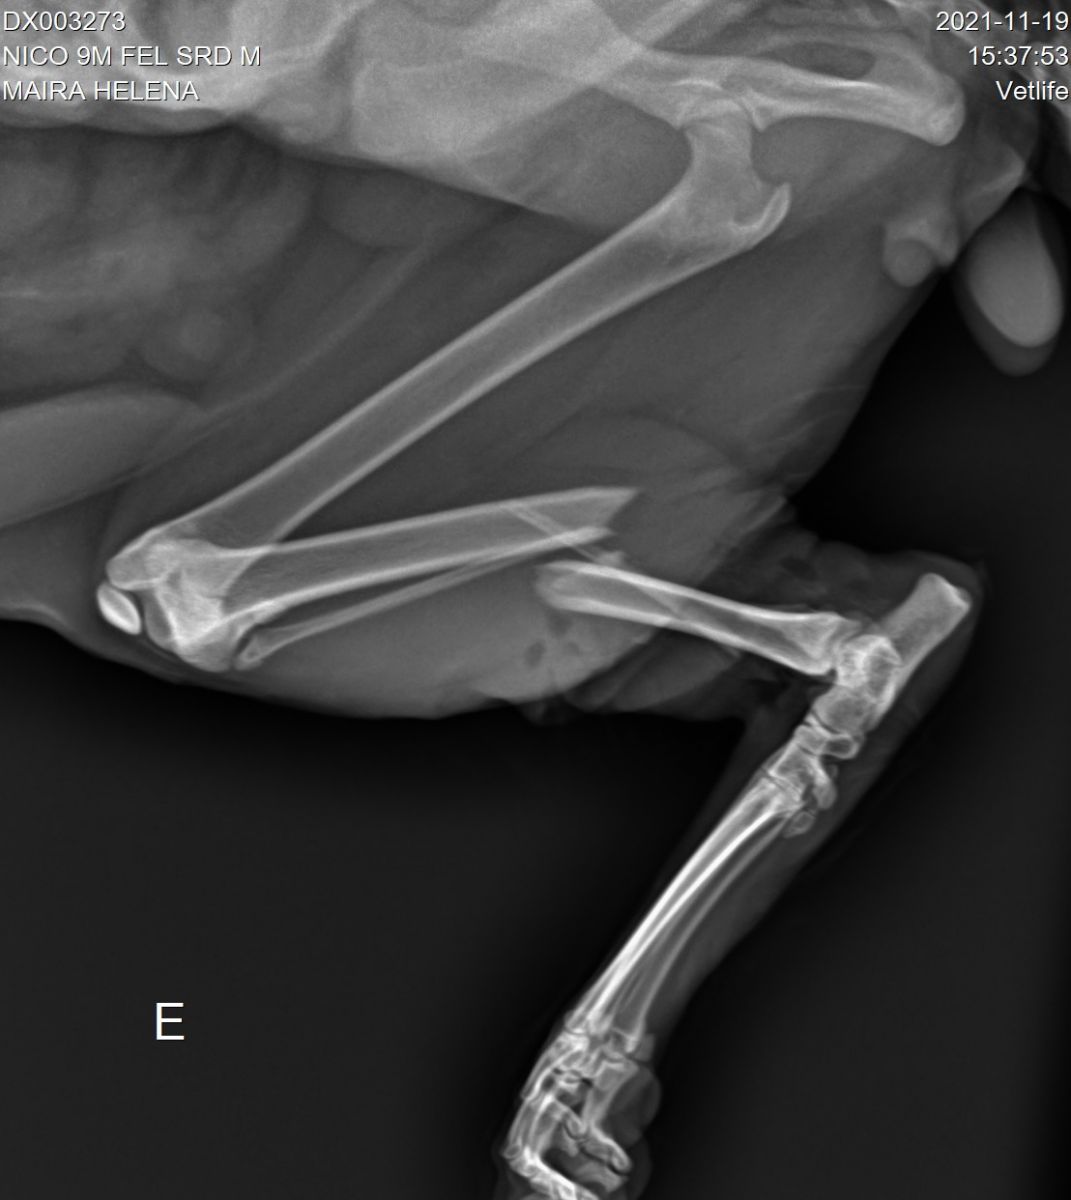

Segundo informações, há quase duas semanas, Niko amanheceu sentindo dores e deixou os donos preocupados. O animal foi levado ao veterinário e lá foi constatado um osso quebrado, que pode perfurar os nervos e a carne.

Para reverter essa situação, se faz necessário, um procedimento cirúrgico que custa 1.500 reais. Eles já receberam algumas doações e agora faltam apenas R$ 330.